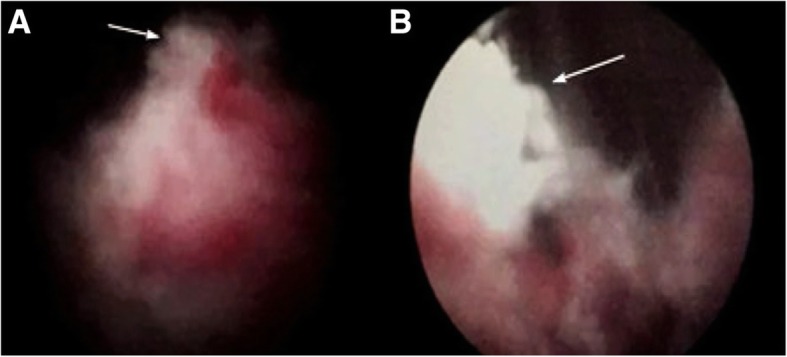

Diagnostic electrocision of urethral mass: after successful subdural anesthesia, our patient took the lithotomy position and the operative area was disinfected with Iodophor (iodine complexed with a solubilizing agent). The operator inserted a 22.5F Karl Storz resectoscope into her bladder. The bladder was observed and the operator found congested trigone of the bladder, which might have been the result of catheterization. The operator used the resectoscope in a retrograde manner to reach the neck of her bladder, which showed the direction of 3–5 points of neoplasm protruding into the bladder, and 6–9 points direction of new neoplasms growing into the urethra and extending to the external urethral orifice. The new neoplasms were crispy and easy to peel and contained visible bleeding. The operator cut surface necrosis with an electric cutting ring, and electrocoagulation was used to stop bleeding followed with flushing out of the specimens. After examination of the complete urethra without obvious residue, an indwelling 20# catheter was inserted; the operator gave local mild compression and connected the catheter with physiological water to flush the bladder (Fig. 1).

Fig. 1.

Cystoscopy performed in April 2015. The neoplasm is located in the posterior urethra (arrow) (a). It extends beyond the urethra (arrow) (b) into the bladder neck and is dark red, easily bleeding. The doctor took a biopsy. (magnification, × 5)